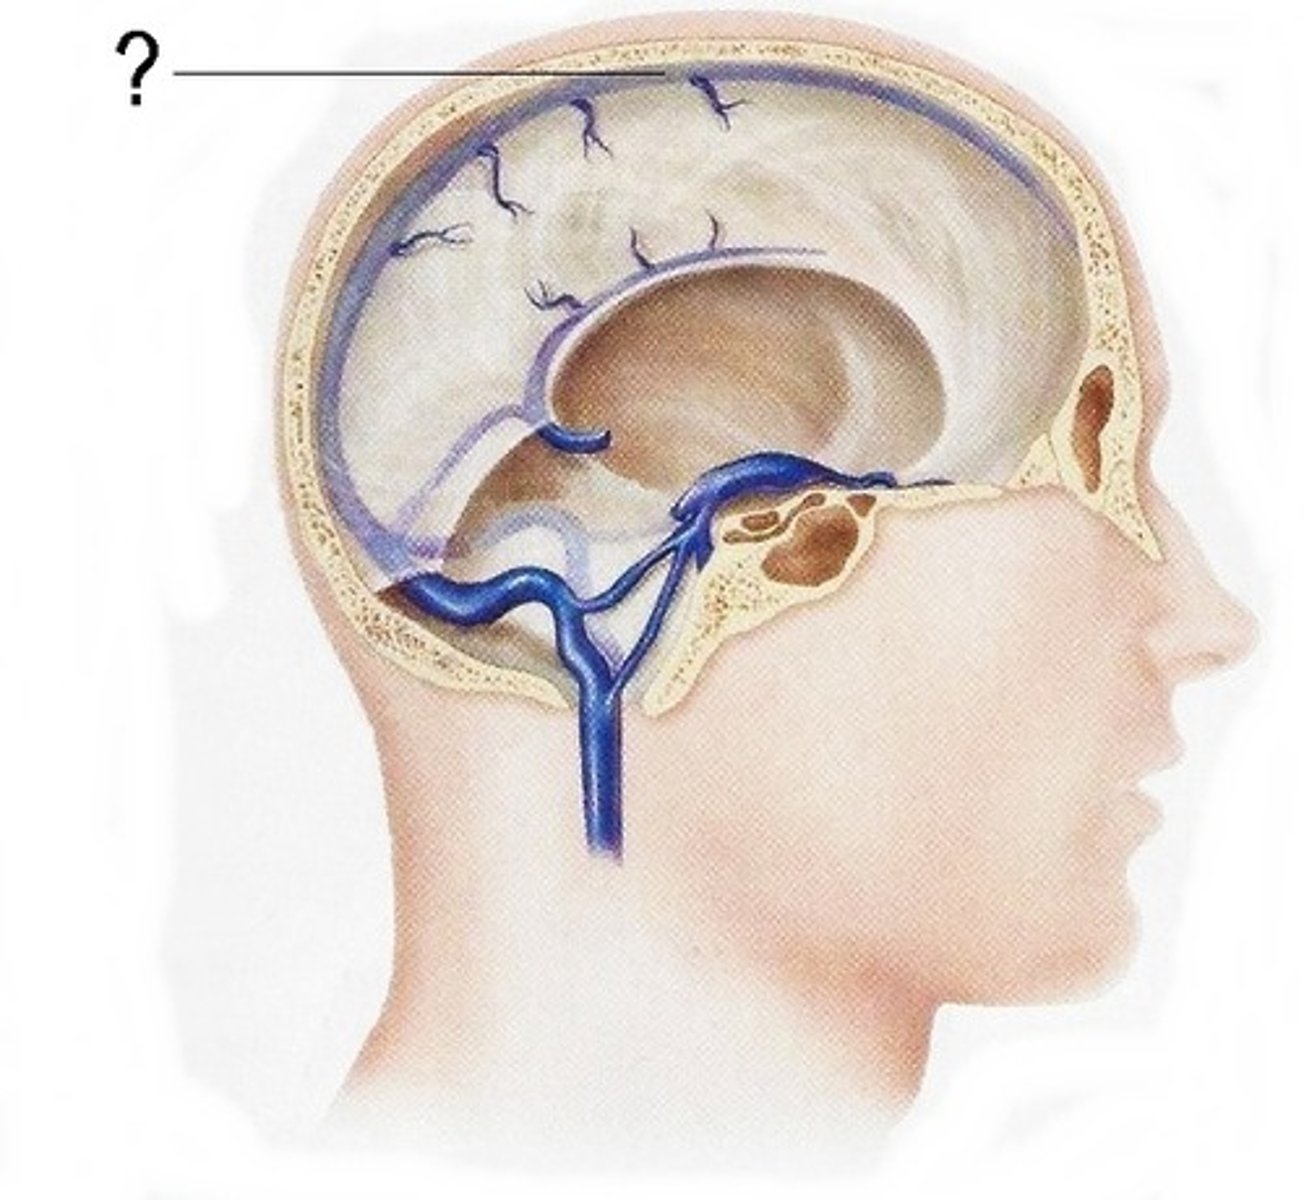

arachnoid villus

superior sagittal sinus

arachnoid mater

dura mater

pia mater

subarachnoid space